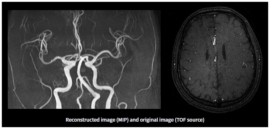

반면에 MRA(자기 공명 혈관 영상)는 MRI의 일종으로, 혈관의 이미지를 생성하는 데 초점을 맞추고 있습니다. 이는 혈관의 구조 및 흐름을 평가하는 데 유용하며, 주로 심혈관 질환의 진단에 사용됩니다. MRA는 특히 혈관의 협착이나 막힘, 동맥류와 같은 혈관 관련 문제를 발견하는 데 매우 유용합니다.

MRA는 MRI의 기법을 기반으로 하므로, 기본적으로는 동일한 작동 원리를 가지고 있지만, 약간의 차이점이 있습니다. MRA는 특히 혈관을 시각화하는 데 최적화되어 있으며, 주로 조영제를 사용하여 혈관을 더욱 뚜렷하게 구분합니다. 조영제는 혈관 내에서 신호의 차이를 만들어 신호 강도를 높여줍니다. 이로 인해 혈관의 형태와 상태를 더욱 명확하게 시각화할 수 있습니다.